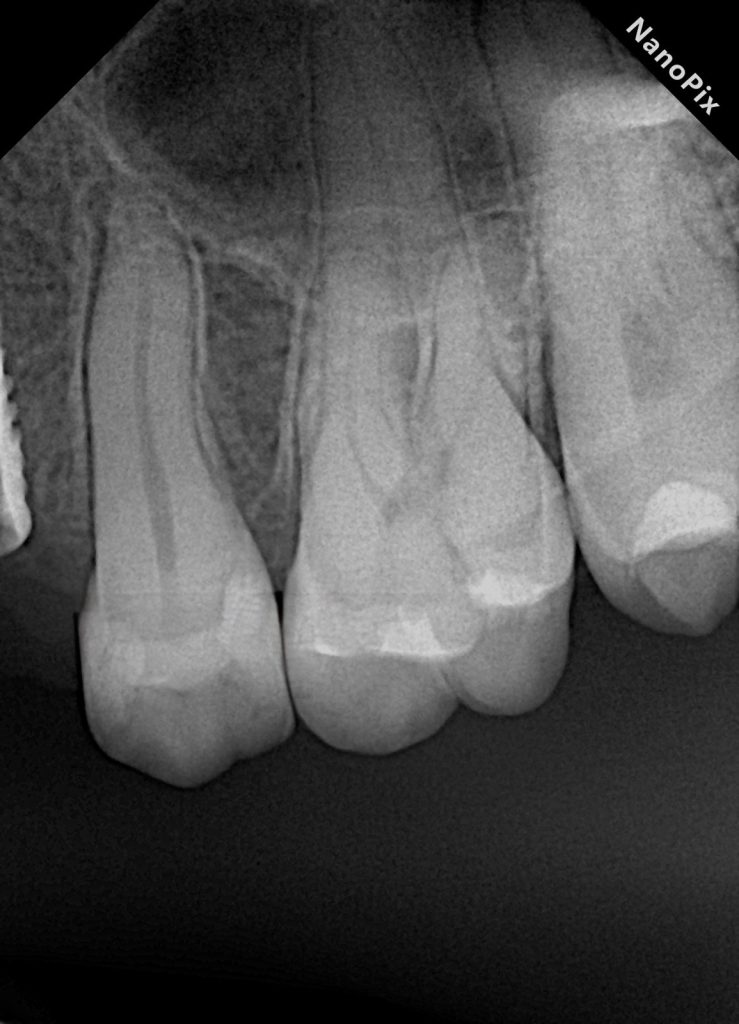

9) Radiographic verification

Step 19: Post-op bitewing/periapical

Assess:

- No overhangs

- Proper marginal seal

- Anatomical contour

- Contact area (indirect sign: no obvious open contact + correct contour)

Images to place

- Fig. 14: Post-op radiograph.